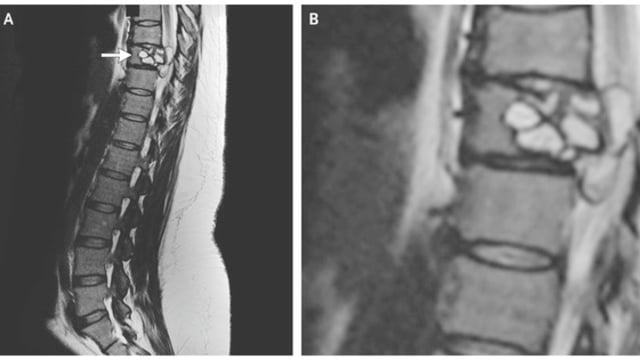

Saat diperiksa oleh para dokter di Centre Hospitalier Universitaire de Dijon, Prancis, ditemukan adanya luka pada tulang belakangnya, tepatnya pada bagian tulang punggung kesembilannya. Ternyata luka itu disebabkan oleh parasit Echinococcus granulosus, cacing pita yang biasa ditemukan pada anjing serta beberapa hewan ternak seperti domba, sapi, kambing, dan babi.

Luka akibat parasit Echinococcus granulosus ini biasanya ditemukan di hati atau paru-paru. Tapi selain di kedua organ tersebut, luka ini juga bisa ditemukan di bagian tubuh lainnya. Meski demikian kasus infeksi pada tulang dan tulang belakang seperti yang terjadi pada wanita Prancis ini langka terjadi.